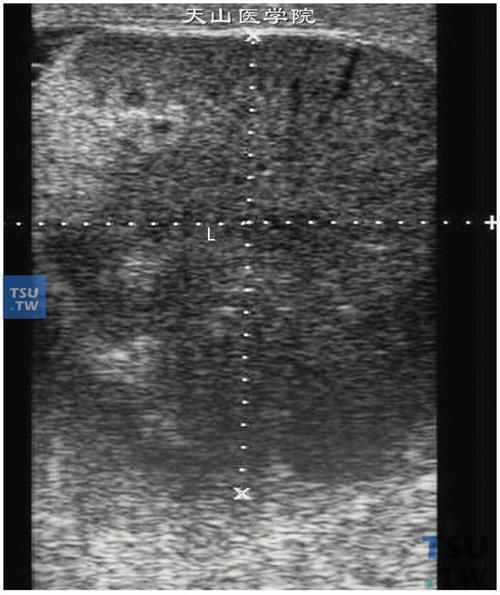

睾丸扭转之鞘膜外型——双环征